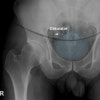

- Shenton line이 정상적인 부드러운 선이 아니라고 하는 것은 femoral neck fracture를 의미합니다. 전위되지 않은 대퇴경부 골절은 발견하기 쉽지 않습니다.

① Symphysis pubis width should be no more than 5mm in adults, 10mm in children

② >5mm indicated disruption & AP compression injury

③ Superior displacement suggests vertical shear injury

④ Overlap may suggest lateral compression injury